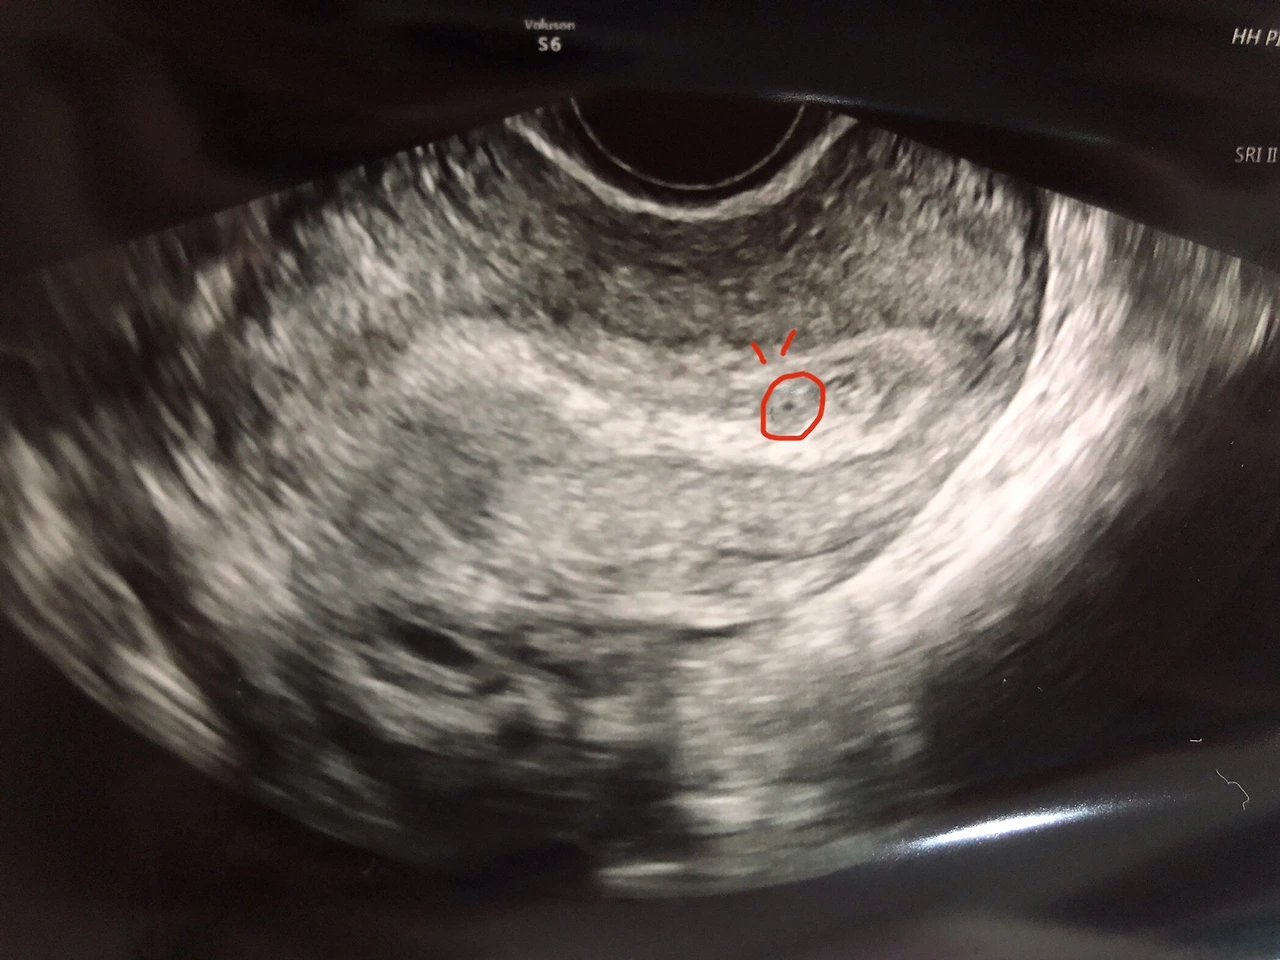

초음파 사진 때, 너무 작아서 콩알 만해서 붙였던 이름. 알콩이.